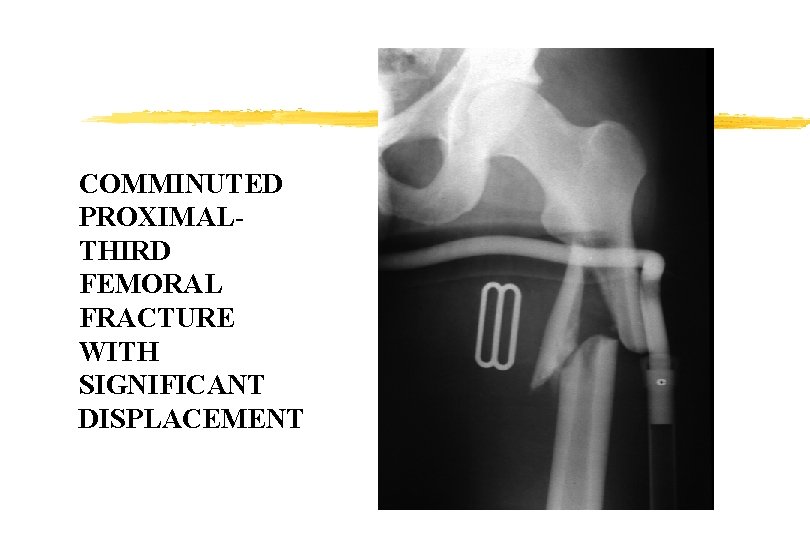

COMMINUTED PROXIMALTHIRD FEMORAL FRACTURE WITH SIGNIFICANT DISPLACEMENT